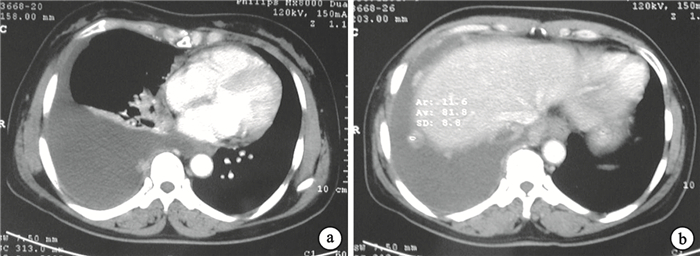

入院后查外周血白細胞9.2×109/L,中性粒細胞72%,血沉51 mm/1 h。多次查痰抗酸染色陰性,結核抗體陰性。血漿總蛋白80 g/L,白蛋白39 g/L,乳酸脫氫酶236 IU/L。癌胚抗原(CEA)31.38 μg/L(正常值<5 μg/L),癌抗原19-9(CA19-9)753.90 U/mL(正常值<37.0 U/mL),癌抗原125 (CA125)73.04 U/mL(正常值<35 U/mL)。動脈血氣分析:pH 7.471,二氧化碳分壓41 mm Hg,氧分壓56 mm Hg,吸入氧濃度21%。胸腔穿刺胸腔積液檢查:胸腔積液外觀呈深黃色,比重1.031,細胞總數1.2×109/L,有核細胞數0.7×109/L,單核細胞78%,多核細胞22%;總蛋白45 g/L,白蛋白 28.7 g/L,乳酸脫氫酶236 IU/L,葡萄糖9.52 mmol/L,腺苷酸脫氨酶14 U/L,癌胚抗原295.30 ng/L,胸腔積液培養陰性,胸腔積液涂片未找到抗酸桿菌及腫瘤細胞。胸部增強CT示右側大量胸腔積液,右肺壓迫性肺不張,右側胸膜可見增厚和多發結節伴強化(圖 3)。